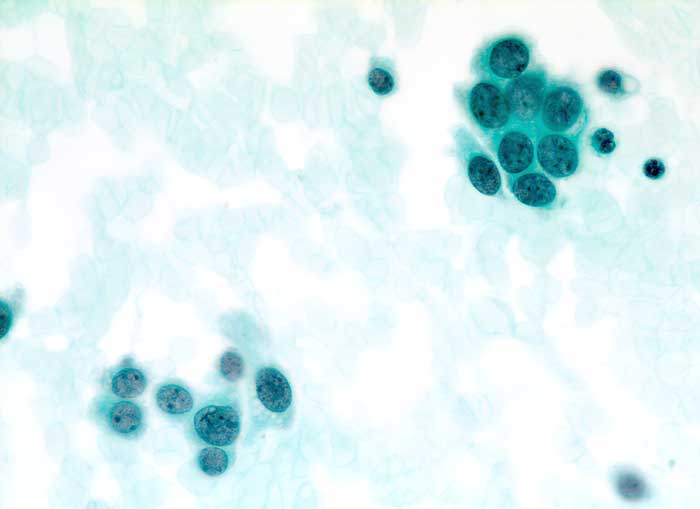

PathoPic – image database / PathoPic ID 5589 - Duktales Carcinoma in situ

Duktales Carcinoma in situ

Feinnadelpunktion Mamma: Kleine Zellverbände. Die atypischen Zellen erscheinen monomorph und wenig grösser als normale Mammaepithelien.

Zytologische Diagnose: Zahlreiche Karzinomzellen. Kommentar: Der zytologische Befund, insbesondere die Monomorphie der Tumorzellen passt gut zu einem duktalen Carcinoma in situ.

500